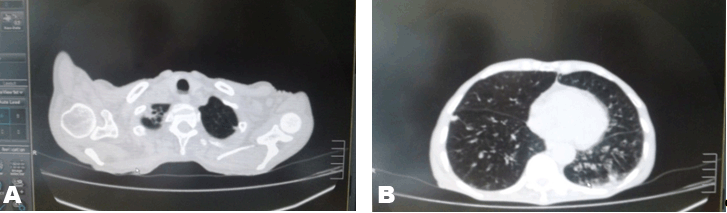

A 66-year-old male, resident of Kamalapuram, a small town in Kadapa region of the Andhra Pradesh (India), presented to General Hospital on 11 April 2014. His chief complaints were progressive breathlessness from last two weeks, pedal edema, fever, headache, cough with sputum, abdominal pain prior to admission. He was an ex-smoker and alcoholic. On examining the patient, he was a lean built man with significant dehydration. His temperature was 100oF, pulse rate 90/min, blood pressure 150/90 mmHg. He maintained a saturation of 93 on ambient air and respiratory rate 24/min. There were few exacerbation in left lower zone. He had no icterus and there was no significant lymph adenopathy. Epigastrium tenderness was observed in the patient. The liver, spleen and kidneys were not palpable. Patient's Medication History and Treatment Investigations Treatment | ||||||